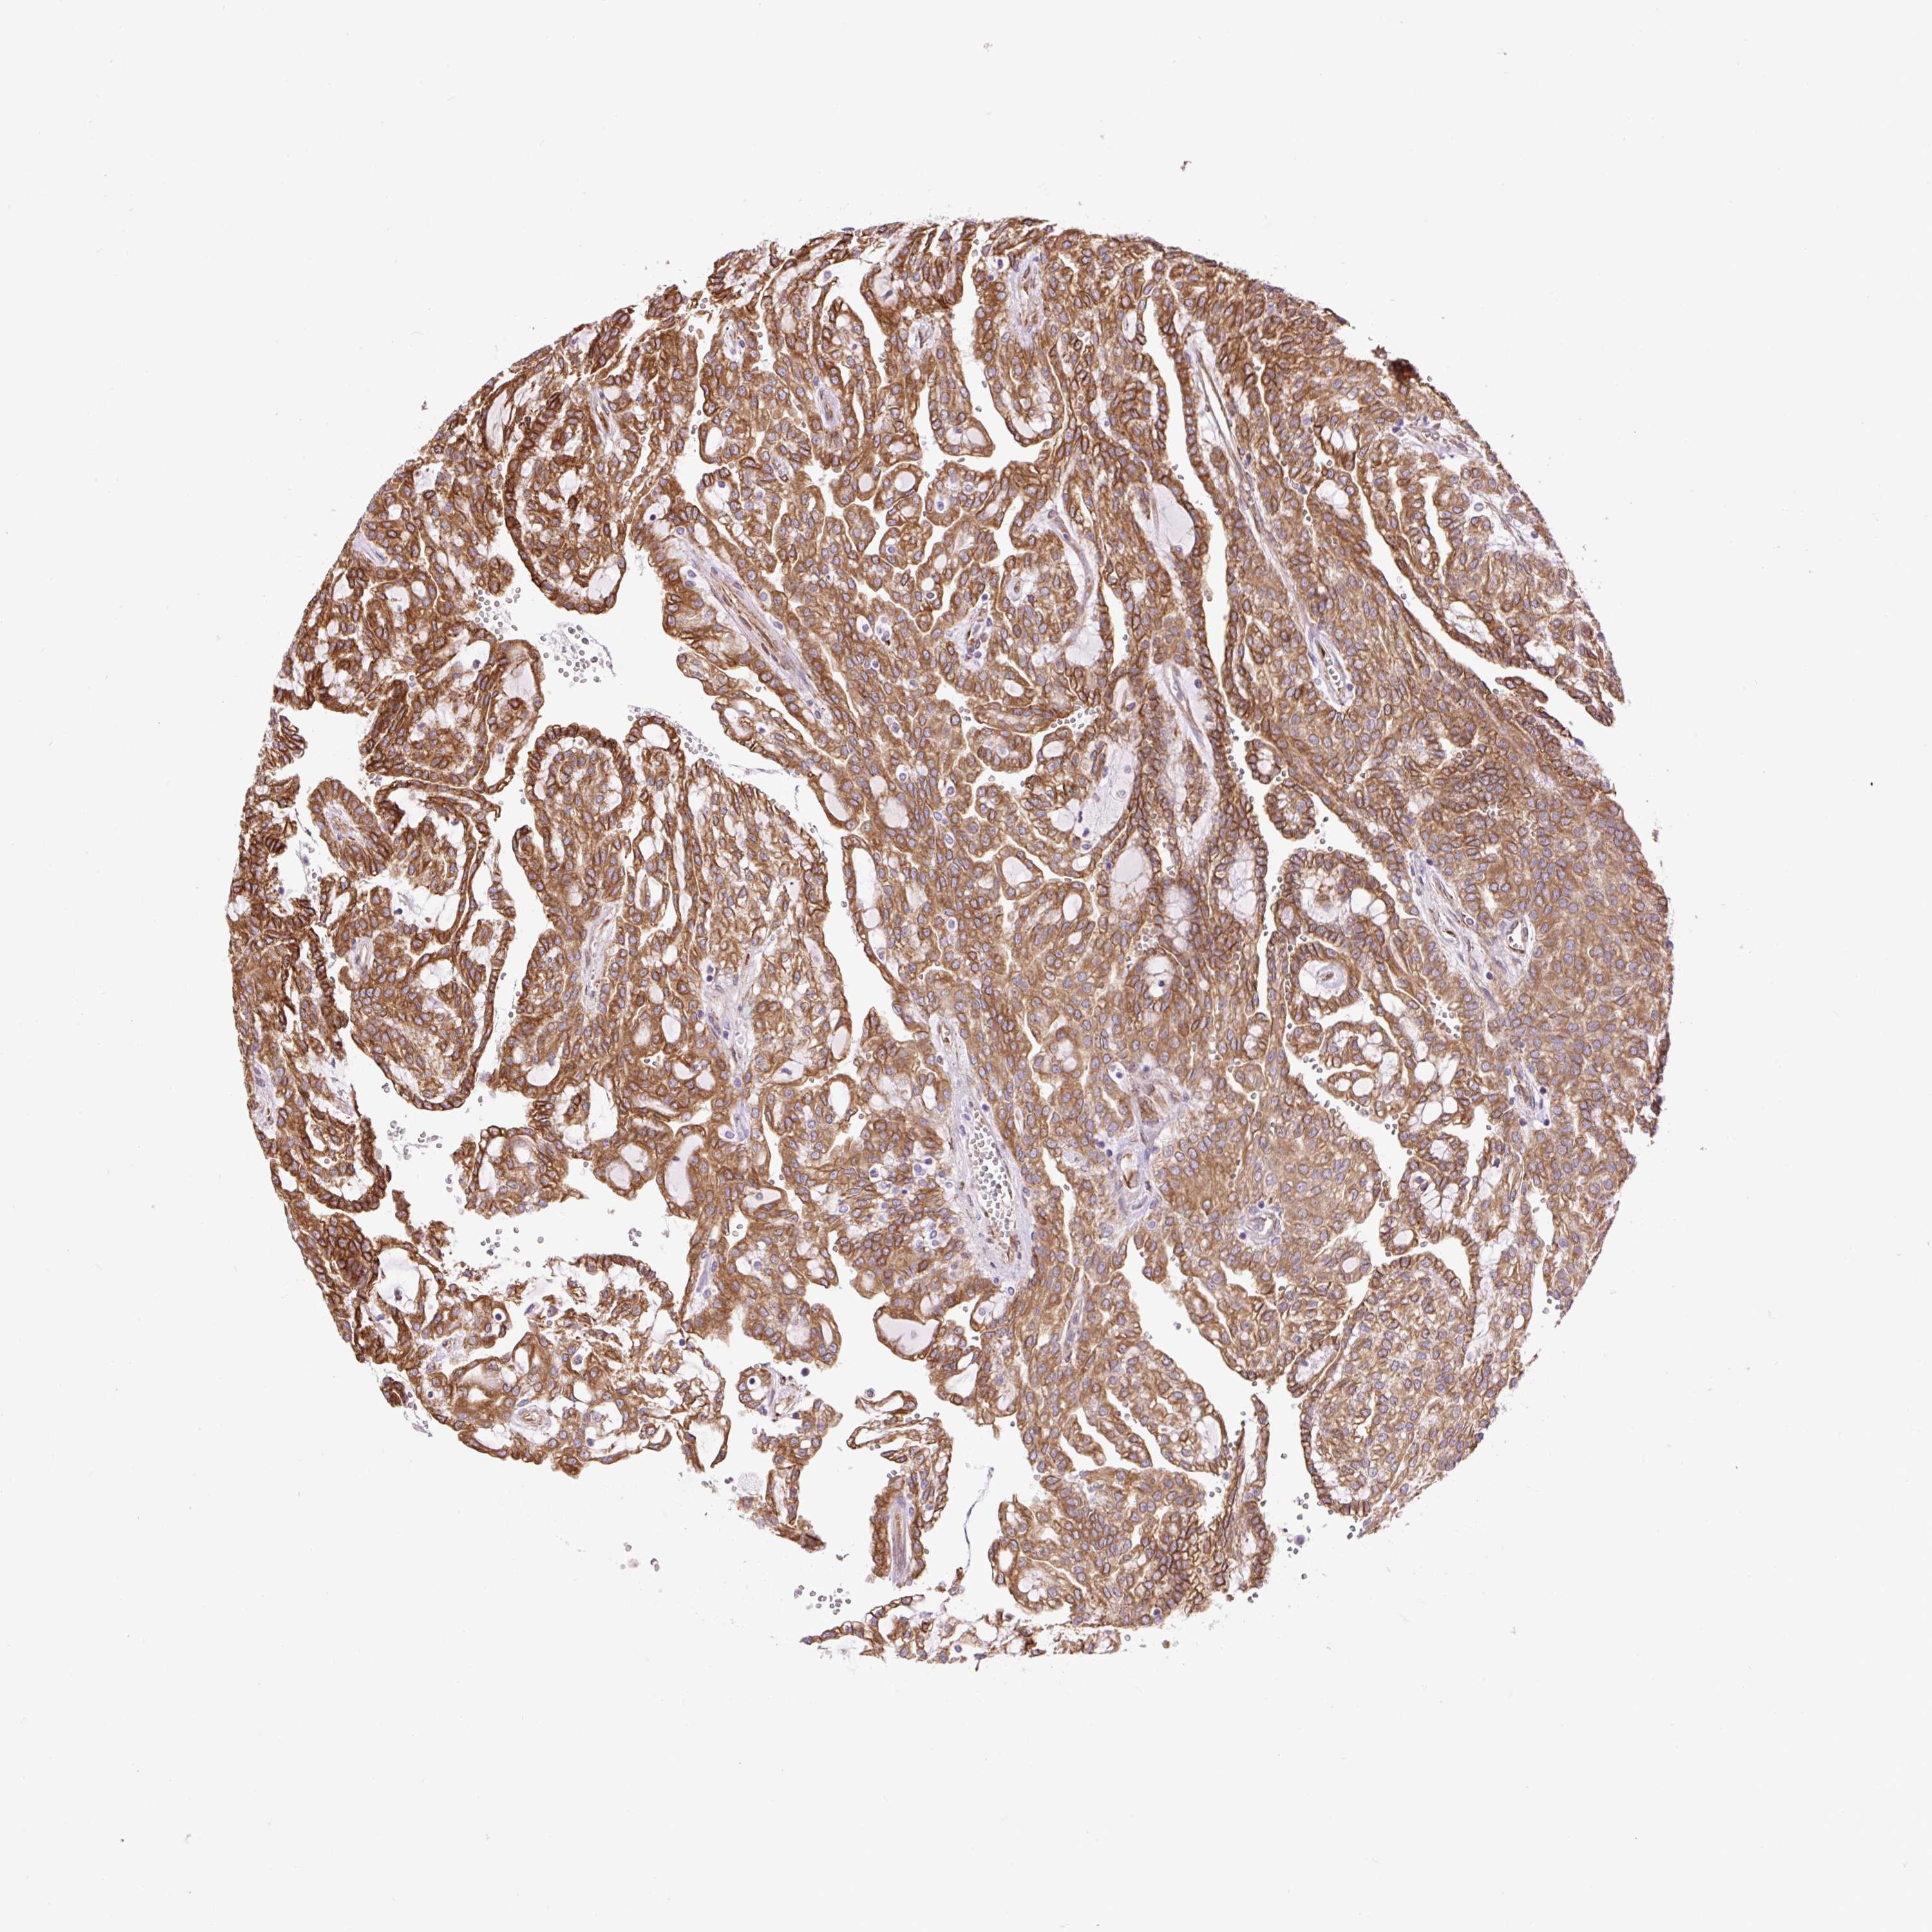

ANTIBODIES

AND

VALIDATION